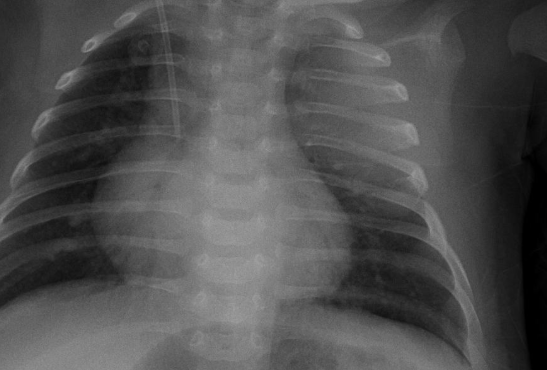

기흉이 심해지면 흉막강 내 공기가 계속 축적되어 폐와 심장을 압박하는 긴장성 기흉이 발생할 수 있는데, 이 상태는 생명을 위협하는 응급상황으로 혈압 저하, 청색증, 의식 저하 등이 나타나며 즉각적인 응급조치가 필요합니다. 진단 방법은 보통 흉부 X선 촬영으로, 허탈된 폐와 흉막강 내 공기를 확인하며, 더 정밀한 원인 분석과 확진을 위해 흉부 CT를 시행하기도 합니다. 청진 시에는 기흉이 있는 쪽 가슴에서 호흡음이 감소하거나 사라진 점도 진단에 도움이 됩니다.